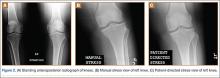

The protocol for obtaining the patient-directed valgus stress view of the knee is as follows: The patient lays supine with a dense 45º spine-positioning wedge (Burlington Medical Supplies) placed under both knees and the patient’s heels on the examining table. The radiographic tube is angled cephalad 7º to 10º centered on the inferior pole of the patella, using a 40-in source to image-receptor distance, collimated to part; the image receptor is placed under the affected knee, below the positioning wedge. The affected knee is rotated to the “true” AP position (the patella will be centered between the femoral condyles on the AP exposure), and the ball is placed between the patient’s legs just above the ankle joint. The technologist demonstrates to the patient how to squeeze the ball while maintaining contact of heels with the table. The technologist can exit the room and obtain the exposure, which is taken while the patient is squeezing the ball, as shown in Figures 1A and 1B. Examples of the standing AP, manual stress, and patient-directed valgus radiographs are shown in Figures 2A-2C. The entire technique is demonstrated in the Video.